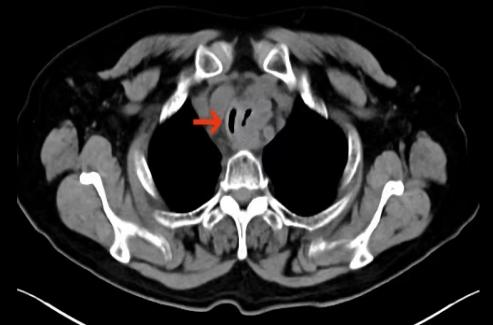

CT下见主支气管极重度狭窄